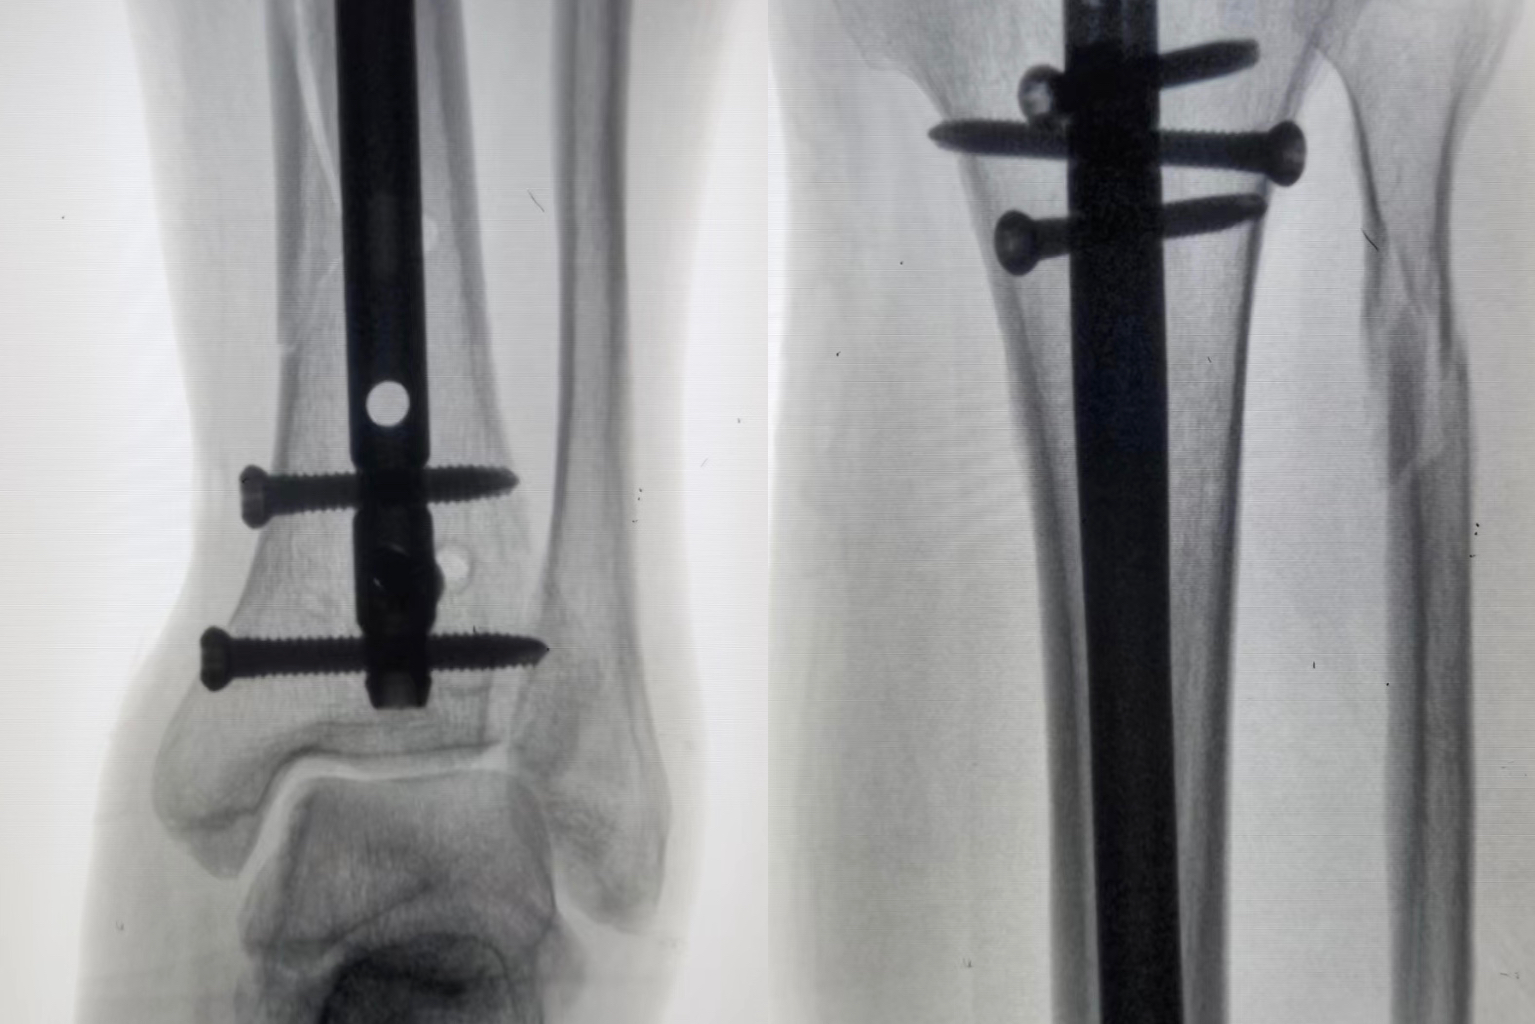

病例一:患者,女,70岁,车祸致左肱骨近端粉碎骨折,在孙院长组织术前讨论后决定行”左肱骨近端粉碎性骨折闭合复位髓内钉内固定术”考虑患者年龄大、基础病较多,微创治疗恢复快,骨三科医疗团队为其行手术治疗,术后功能恢复良好,患者及家属十分满意。 ▲术前 ▲术后 病例二:患者,男,51岁,因滑倒摔伤致左胫腓骨骨折伴后踝骨折,术前准备钢板内固定、髓内钉闭合内固定两种手术方案,通过术前讨论和局部皮肤条件的观察,选用髓内钉闭合复位内固定,骨三科医疗团队主刀下运用多枚克氏针(阻挡+固定+合拢),解决后踝和螺旋劈裂骨折块问题,手术顺利结束。 ▲术前 ▲术后 ▲术后 ▲术后微创小切口 目前,我院骨三科医疗团队已成功完成数例髓内钉手术,临床疗效非常满意。近年来周口人合医院骨三科大力发展微创技术,积极开展各类微创手术,力求打造微创以及快速康复的治疗新标杆,更好地为人民健康保驾护航。 ▲创伤与手足显微外科专家查房查看患者病情 ▲创伤与手足显微外科专家共同探讨患者病情